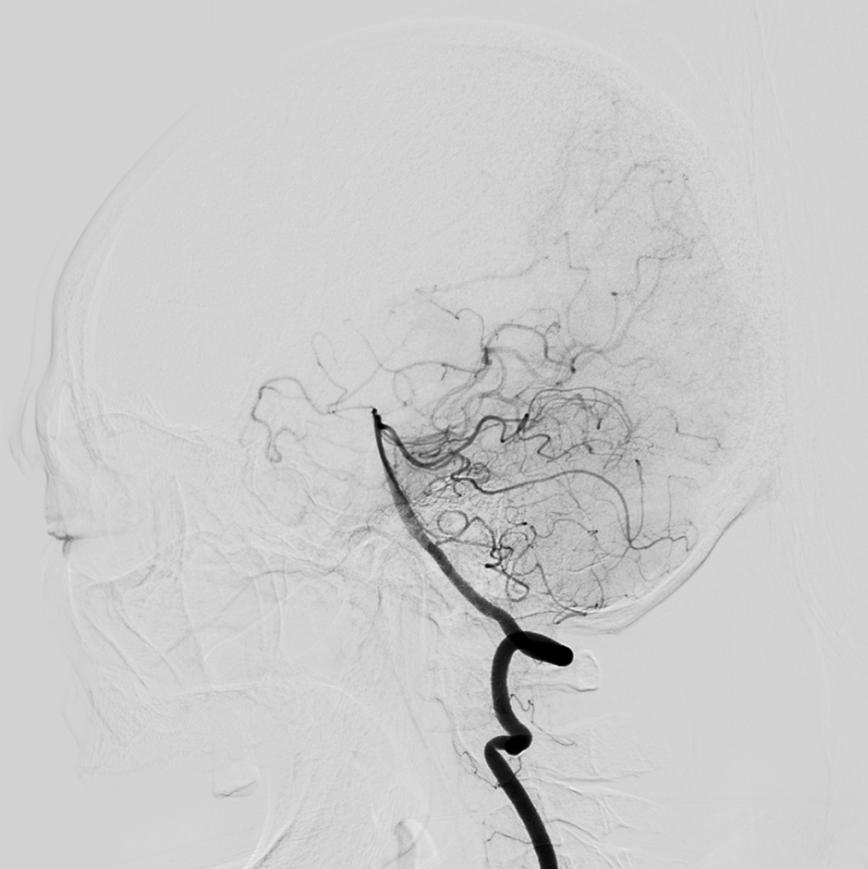

流行病学研究基本上将脑卒中分为出血性卒中和缺血性卒中两大类。出血性脑血管病包括:颅内动脉瘤、脑血管畸形、高血压脑出血等。

缺血性脑血管病包括各种病因如颅内动脉狭窄、颈动脉狭窄、椎动脉狭窄、锁骨下动脉狭窄、烟雾病(Moyamoya病)、动脉粥样硬化疾病或心源性疾病导致的脑缺血。在我国急性缺血性脑卒中是最常见的卒中类型,约占脑卒中的69.6%~70.8%,在空间分布上有北方高、南方低的趋势,这与高血压患病率的空间分布几乎一致。急性缺血性脑卒中的处理包括早期诊治、早期预防再发(二级预防)和早期康复。随着医疗技术水平的提升及医学材料科学的进步,缺血性卒中的治疗由早期的静脉药物溶栓治疗发展为血管内溶栓、急诊支架取栓等多种治疗方式。而对于预防缺血性脑卒中事件的发生,颈动脉内膜剥脱术、脑血管搭桥手术、责任血管的球囊扩张加支架置入术等多种治疗方案亦发挥着不可替代的作用。